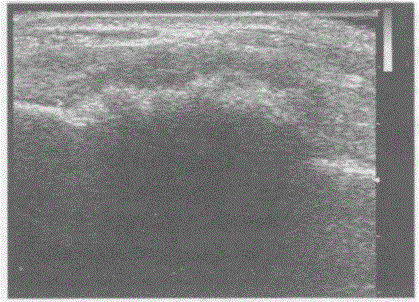

问题 临床资料:20岁,女,自述左腕部肿痛,发现肿物两月余。 超声综合描述:左腕部扫查骨皮质连续中断,呈虫蚀样,可见6.7cm×2.2cm不均质回声区,中部回声强,周边回声低,CDFI:内见伸入支血流信号。见下图及彩图123。 {图2} {图3} 超声提示: